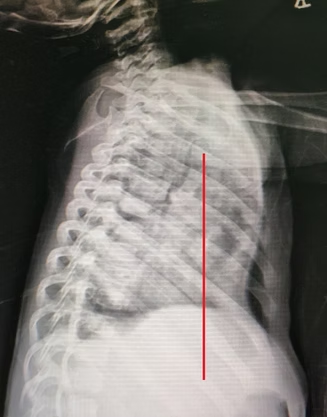

As chest wall bones become increasingly stiff with age, both the difficulty and risks of correcting chest wall deformities increase. Therefore, although there is no universal standard for the optimal timing of pectus excavatum surgery, clinical experience indicates that early intervention is typically more effective due to the greater pliability of the chest wall in infants and young children.

Dr. Wenlin Wang‘s new method—Wang procedure, overcomes the conventional age limits, allowing patients to receive treatment before their teenage years. This method is safe for babies as young as one month old because it puts the shaping bar on the surface of the chest wall bones instead of inside the chest cavity, thus avoiding damage to the heart and lungs. Surgery on children during these years is easier on the bones, which means less pain after surgery and a faster recovery than surgery on adults with stiff chest walls.

Taking care of the deformity early stops the condition from getting worse. As a person gets older, the thoracic depression usually gets worse, especially during growth spurts. This makes the bones in the chest wall harder, which makes future surgery harder and more dangerous. In the Wang procedure, the metal bar is placed on the surface of the chest wall bones, and only its middle section is fixed, so it generally does not hinder the normal development of the chest wall. This helps the chest wall bones grow normally during puberty and reduces the risk of deformity recurrence.